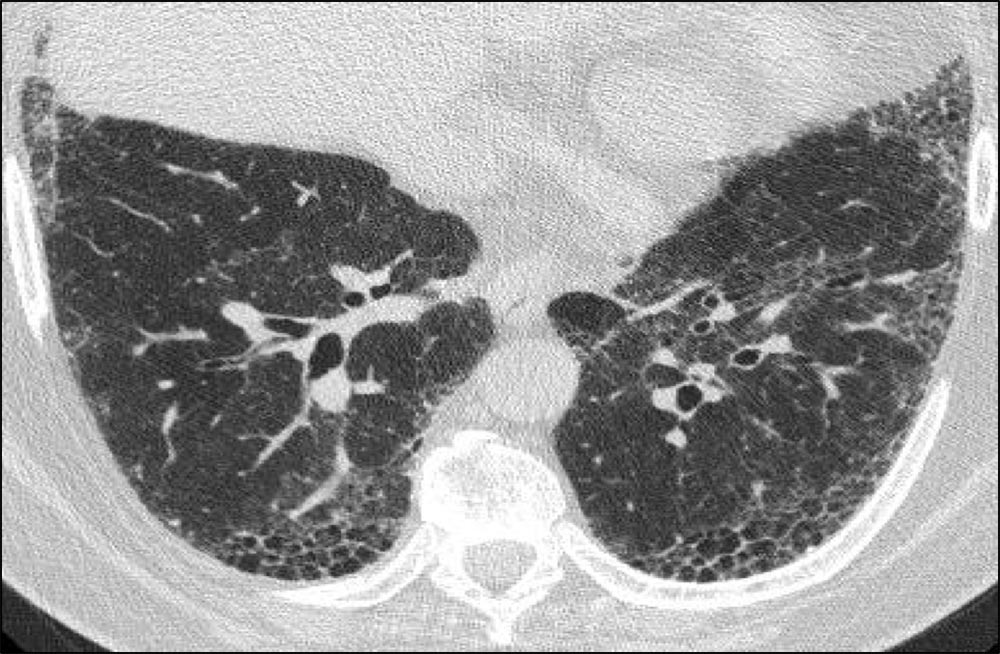

Axial HRCT showing significant honeycombing in a predominantly subpleural pattern at the bases of the lung with peripheral reticulation and traction bronchiectasis. Note the asymmetric pattern of fibrosis, a hallmark feature of usual interstitial pneumonia (UIP).